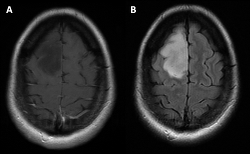

A 43-year-old otherwise healthy woman develops new-onset stereotyped convulsive activity of the left face and arm. The episodes last approximately 30 seconds and resolve without intervention. She is afebrile and has no other signs of infection. There is no preceding history of trauma. Her neurological examination is unremarkable. There was no evidence of intracranial hemorrhage on computed tomography. Magnetic resonance imaging reveals a large right frontal area of increased signal on fluid-attenuated inversion recovery (FLAIR), which does not enhance on postcontrast imaging (Fig 1). She undergoes craniotomy with gross total resection of the lesion. The pathology reveals increased cellularity, abnormal nuclei, mitoses, and a lack of 1p19q co-deletion in the abnormal cells. There is no inflammatory infiltrate present. Endothelial proliferation and necrosis are also not present.

Figure 1 - Click to enlarge in new windowFIGURE 1. Axial magnetic resonance images of (A) T1 postcontrast sequences and (B) fluid-attenuated inversion recovery